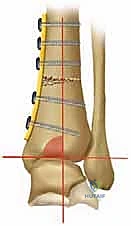

| قطع العظم فوق الكاحل (Osteotomy) | قطع عظم الساق وإعادة توجيهه لتصحيح المحور وتوزيع الحمل على الغضروف السليم. | يحافظ على المفصل الطبيعي، يحافظ على الحركة، يوقف تدهور الخشونة، لا يمنع إجراء الدمج أو الاستبدال في المستقبل إذا لزم الأمر. | يتطلب فترة تعافي أطول لالتئام العظم، يتطلب مهارة جراحية فائقة جداً. | المرضى الأصغر سناً، النشطين، ذوي الخشونة المتركزة في جانب واحد (التقوسية)، مع وجود غضروف سليم في الجانب الآخر. |

التخطيط الجراحي: دقة المليمتر مع الدكتور محمد هطيف

النجاح في جراحة قطع العظم لا يحدث في غرفة العمليات، بل في مرحلة التخطيط التي تسبقها. يستخدم الدكتور هطيف برمجيات حاسوبية متقدمة لتحليل صور الأشعة وحساب زوايا التصحيح المطلوبة بدقة متناهية.